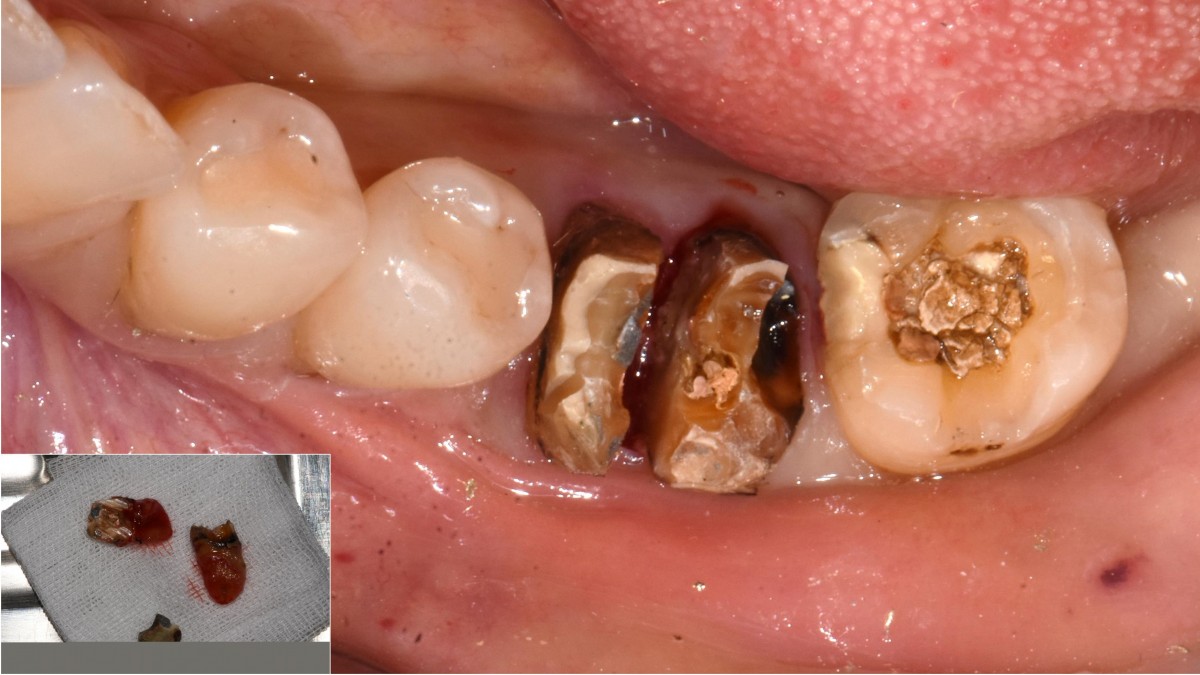

A 51-year-old patient complained of an

old-crowned molar. The lower left molar had a gold crown, and the margin showed discoloration indicative of inner caries. Also, it had furcation-involved periodontitis

with an apical lesion.

Extraction and immediate placement of an implant.